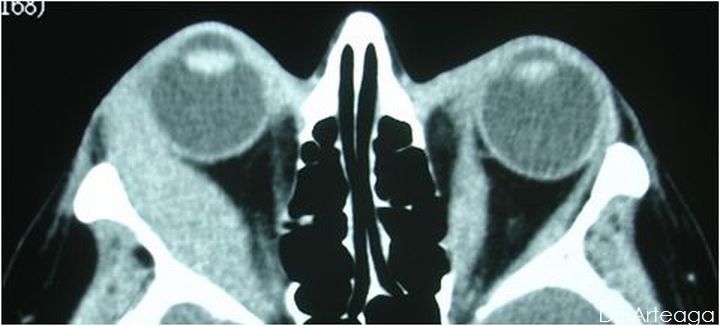

Galería de Imágenes